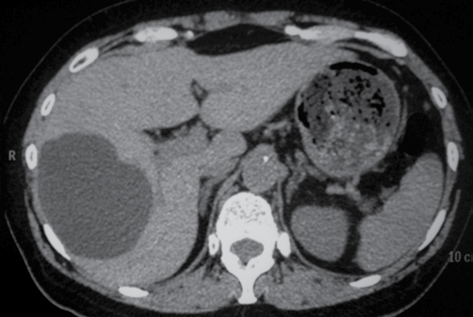

O corte tomográfico computadorizado abdominal sugere

hepatocarcinoma.

nódulo de regeneração hepática.

cisto hepático.

metástase hepática isolada.

adenoma hepático.